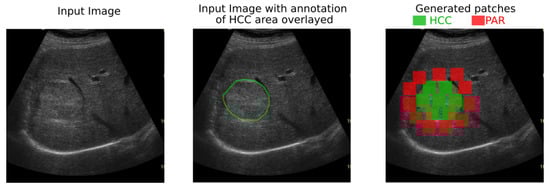

In ultrasound images, HCC usually appears as a hyperechogenic, inhomogeneous structure, due to the interleave of various tissue types, such as necrosis, fibrosis, active growth tissue, fatty cells [1]. As it can be noted from Figure 1, the visual aspect within ultrasound images of the PAR and HCC presents relevant features that characterize textures, such as finesse, coarseness, smoothness, surface granulation, randomness, irregularity.

The human-based analysis of the regions in the ultrasound images made in order to find problematic areas such as HCC or PAR can be aided by an automatic recognition method, such as the one proposed in this paper. The medical specialist could select regions of interest, as shown by the yellow patch in Figure 1 and obtain a probability score, displayed as a color confidence map, for each selected region. The proposed method classifies regions of interest from the ultrasound images and can provide a confidence map over the whole ultrasonographic image.

• Two annotated ultrasound image datasets have been involved in this study. Due to medical and practical patient diagnosis reasons, the images have been collected with two different ultrasound devices (General Electric Logiq 9 and General Electric Logiq 7). The first dataset contains information collected from 200 patients, while the second employs 68 cases. For each patient at least 3 ultrasound images have been annotated by the medical specialists, so the HCC area within the image is well marked (as shown in Figure 1 right). Extensive experiments reveal the conclusion that deep-learning-based models overcome the classical machine-learning techniques bringing an improvement of 17% in sensitivity and an improvement of 20% in specificity.

In both datasets, the HCC was marked as a polygonal area in the image, as shown in Figure 1—right, and Figure 2—middle. For each ultrasound image, considering the marked HCC area, rectangular image patches(regions) have been selected, by means of a controlled sliding window procedure. Part of these patches are located inside the annotated area and they correspond to the HCC class. The samples of the generated patches are depicted in green in Figure 2. Other patches are in the immediate vicinity of the polygonal annotation, but outside the marked HCC area. They correspond to the PAR samples and are shown in red in Figure 2. Cases of healthy patients were not considered because, usually, HCC evolves on cirrhotic liver tissue, for patients already affected by cirrhosis. The medical specialists suggested a focus on these two cases—to make the differentiation between HCC and the cirrhotic parenchyma on which it evolved, while healthy tissues have not been included in this study.

Figure 1. (left) Ultrasound image for which the medical specialist can select a region of interest for which the HCC/PAR confidence is needed; (right) Ground truth area—HCC area inside the large green polygon and PAR on which it has evolved delimited by the red polygon.

Figure 2. Generation of HCC and PAR patches of 56 × 56 pixels by scanning the marked area and its close exterior.